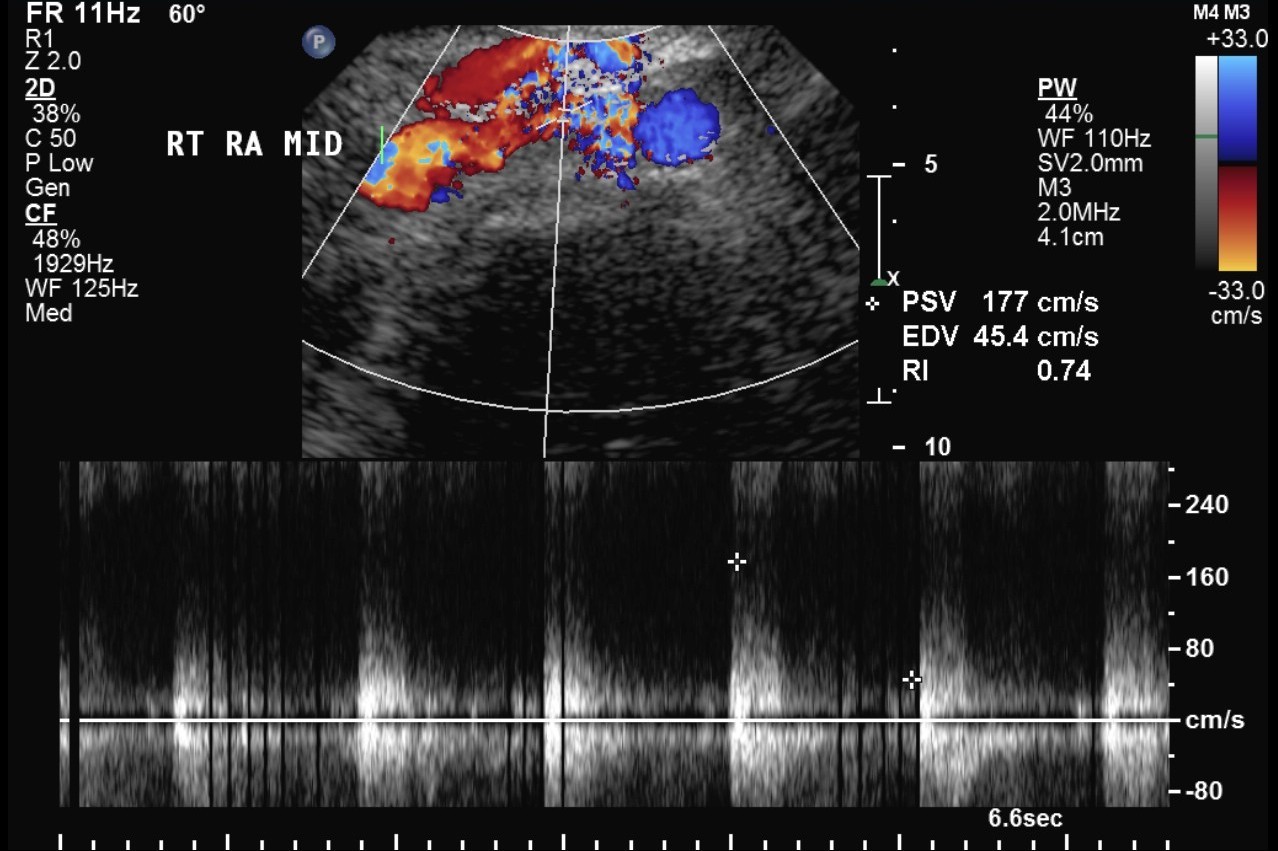

Renal Transplant Duplex Protocol Sonographic Tendencies

From sonographictendencies.com

Renal Transplant Duplex Protocol Sonographic Tendencies Renal Artery Duplex Scan Test This procedure also helps your doctor find blockages in the blood vessels and measure their severity. Summarize the common indications for a renal doppler ultrasound examination for native as well as transplant. The radiologic tests available for diagnosing renal artery stenosis include computed tomographic angiography, duplex doppler ultrasonography, magnetic resonance angiography, and. Our technique for renal duplex examination consists of. Renal Artery Duplex Scan Test.